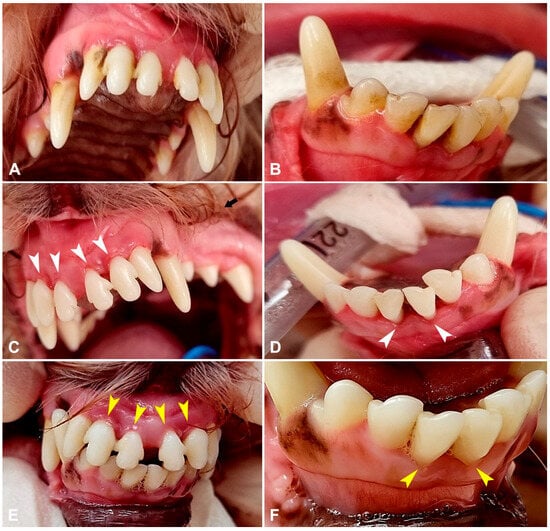

Clinical Evaluation of Autologous PRP (Platelet-Rich Plasma) in the Treatment of Periodontitis in Small-Breed Dogs

Periodontal disease is a progressive inflammatory condition frequently diagnosed in dogs, particularly in small breeds such as Yorkshire Terriers, Toy Terriers, Spitz, Toy Poodles and other breeds predisposed to rapid plaque and tartar accumulation. As the field of regenerative medicine becomes more popular, [...] Read more.

Periodontal disease is a progressive inflammatory condition frequently diagnosed in dogs, particularly in small breeds such as Yorkshire Terriers, Toy Terriers, Spitz, Toy Poodles and other breeds predisposed to rapid plaque and tartar accumulation. As the field of regenerative medicine becomes more popular, more and more attention is being paid to substances that promote tissue regeneration, one of which is platelet-rich plasma (PRP). PRP is an autologous blood-derived product rich in growth factors that stimulate tissue regeneration and modulate inflammation. This study aimed to evaluate the clinical effectiveness of PRP injections without additional activating agents in the management of stage 2–3 periodontitis in small-breed dogs. Forty-two adult dogs (Yorkshire Terriers, Toy Terriers, Pomeranians, Toy Poodles, and Havanese) were enrolled and divided into two groups: PRP (n = 30) and control (n = 12). Following standard dental prophylaxis, the PRP group received gingival, submucosal, and periodontal pocket injections of PRP (0.1 mL per site). Periodontitis stage, gingival index, periodontal pocket depth, and horizontal bone loss were evaluated at baseline and 30 days post-treatment. PRP therapy significantly improved all evaluated parameters (p < 0.05). The gingival index decreased threefold, periodontal pocket depth was reduced twofold, and horizontal bone loss decreased by more than twofold compared with baseline and controls. No adverse reactions, discomfort, or postoperative complications were observed. The administration of non-activated PRP as an adjunct to dental cleaning significantly enhances soft and hard tissue regeneration in small-breed dogs with stage 2–3 periodontitis. PRP therapy represents a safe, minimally invasive, and effective regenerative approach for improving periodontal health in routine veterinary dentistry. Full article